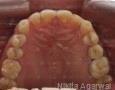

Surgery